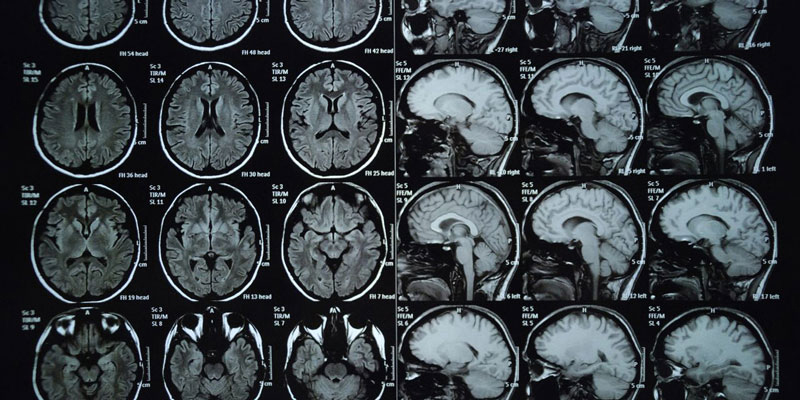

U não là gì?

U não là sự tăng lên và phát triển bất thường của các tế bào trong não dẫn đến hình thành các khối u ác tính hoặc lành tính. Các khối u này có thể hình thành ở nhiều phần ở trong não như lớp lót bảo vệ não, nền sọ, thân não, xoang và rất nhiều khu vực khác liên quan tới não.

Mỗi vùng trong não đều đảm nhận các chức năng khác nhau, vì thế mà các khối u hình thành trong não sẽ ảnh hưởng trực tiếp tới chức năng thần kinh và nhiều hoạt động sống khác của cơ thể.

Có tới khoảng 120 loại khối u có thể xuất hiện trong não, chúng có thể bắt nguồn từ não, từ tế bào đệm của hệ thần kinh trung ương hoặc từ các khối u ác tính trong cơ thể di căn tới não. Từ đó có hai dạng u não phổ biến nhất là u não nguyên phát và u não thứ phát, trong đó u thứ phát hầu như là u ác tính.